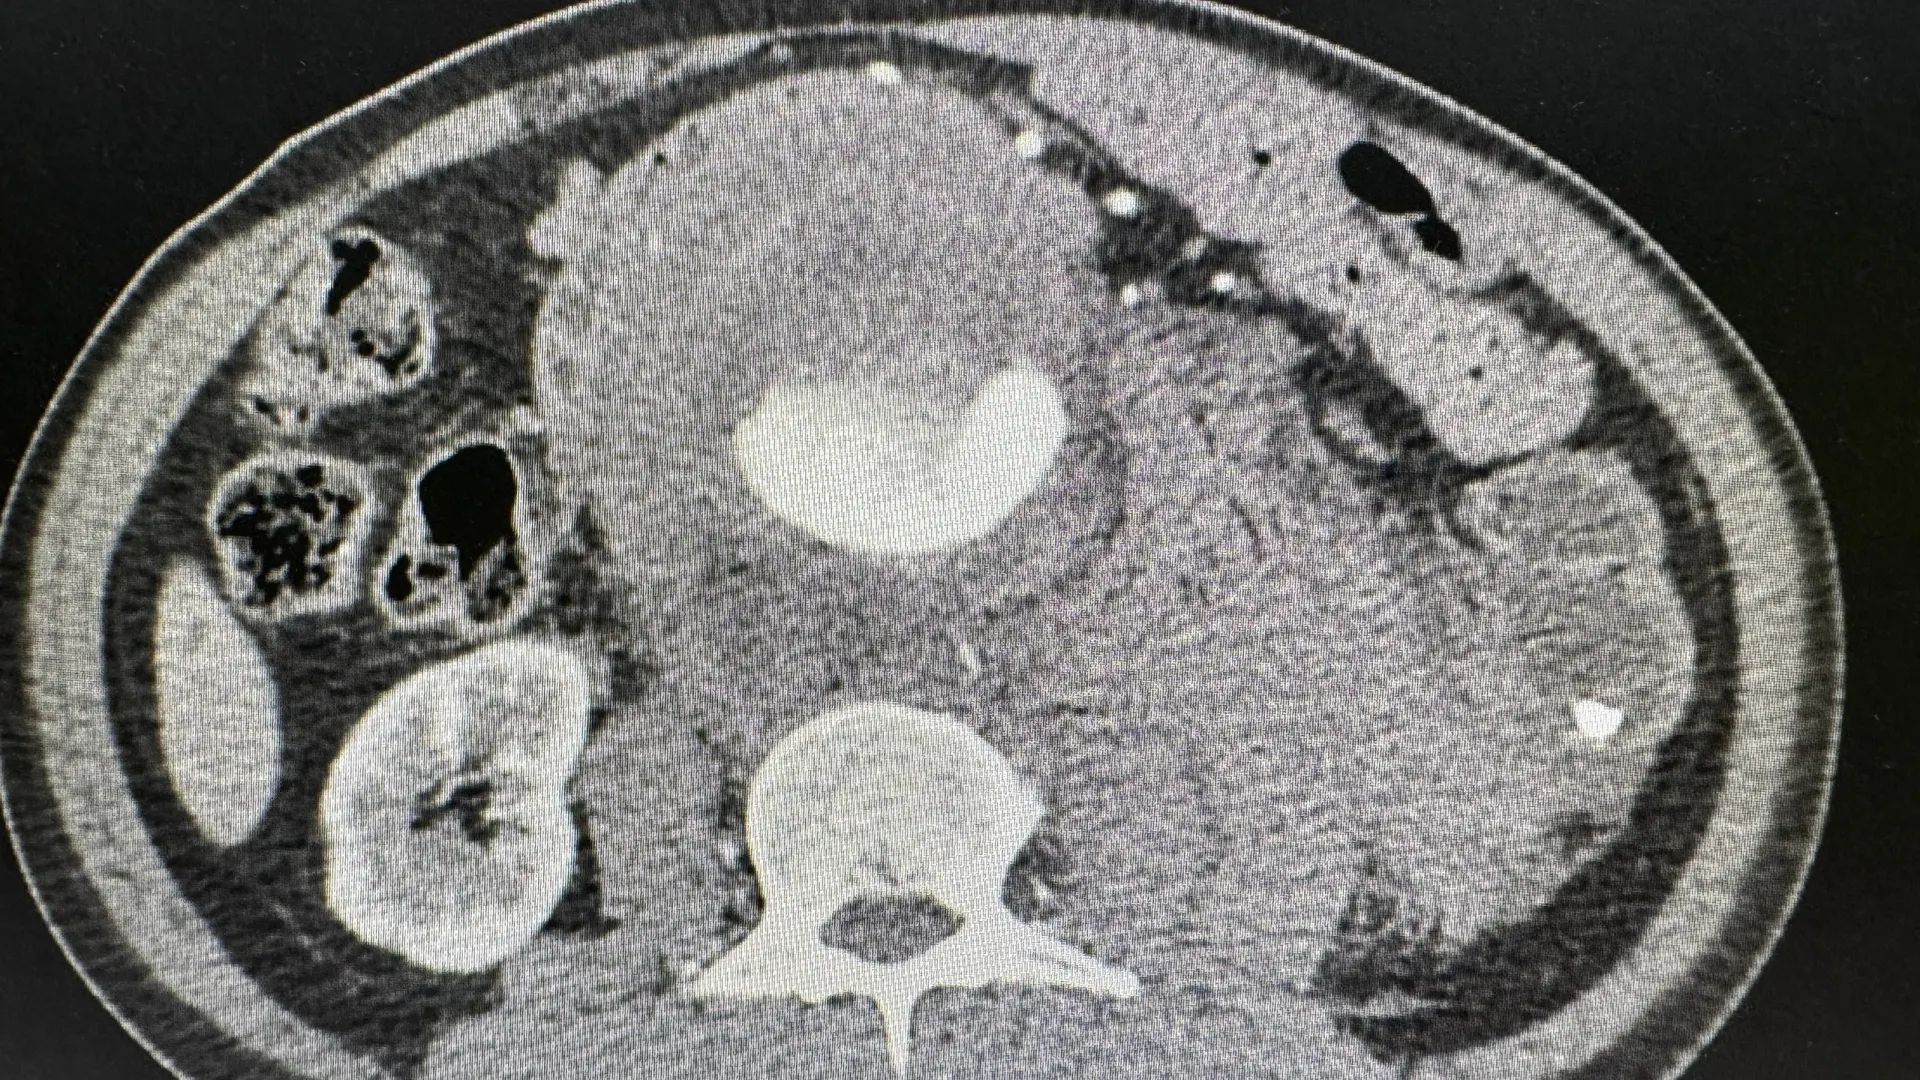

Аневризмой называют расширение этого сосуда, обычно в 1,5–2 раза больше нормальных показателей. Фактически, когда аорта увеличивается, то из полой трубки она превращается в овал или напоминает набухший круг.

Фото: Radiological imaging/Shutterstock/Fotodom

Для диагностики аневризмы аорты медики используют скрининговые методы, такие как рентгенография, которая может обнаружить косвенный признак заболевания. Также проводится эхокардиография, УЗИ сердца, компьютерная томография, магнитно-резонансная томографии, аортография (рентгенологическое исследование с введением контраста, который позволяет выявить патологию), рассказал Денис Прокофьев.